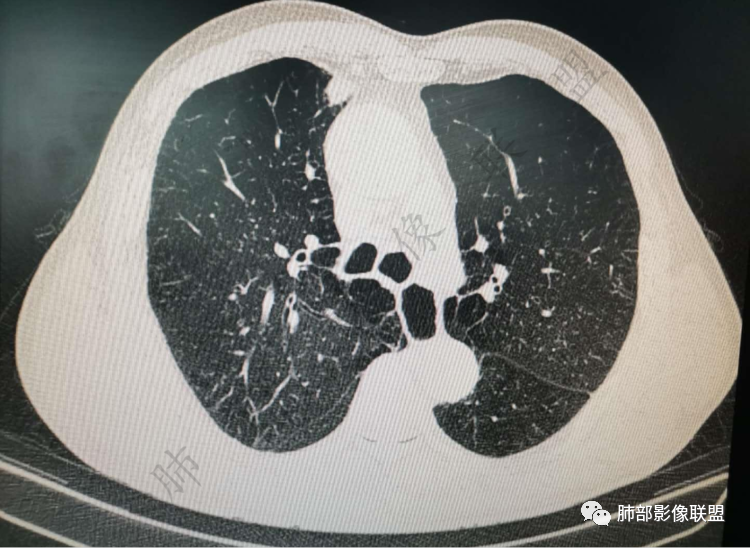

右肺上类圆形叶结节,周边见细软毛刺,增强后呈环形明显强化,内部坏死,邻近胸膜光滑,结合病史2个月明显增大,考虑炎性可能性大。

老年男性,炎性指标略高,肺气肿背景。右肺上叶胸膜下结节,部分边缘平直,部分稍模糊,软长毛刺,血管增粗,病灶中心密度减低,邻近脂肪间隙清晰。考虑炎性肉芽肿或慢性炎症,鉴别鳞癌。

老年男性,炎性指标略高,肺气肿背景。右肺上叶胸膜下结节,部分边缘平直,部分稍膨隆,供血血管增粗,增强扫描病灶中心密度减低,呈环形强化,邻近脂肪间隙清晰。考虑炎性肉芽肿或慢性炎症,鉴别鳞癌。

右肺上叶前段胸膜下结节,边缘分叶毛刺,血管集束,支气管截断,纵膈胸膜牵拉,内乳动脉增粗,密度不均,中央可见坏死,两个月短期随访结节有增大,考虑恶性,腺癌。鉴别结核。

肺气肿背景,右肺上叶纵隔旁胸膜下结节,有血管集束,支气管堵塞,内乳动脉增粗,增强不均匀强化,内可见低密度区。考虑为恶性可能性大

老年男性,肺气肿背景,右肺上叶胸膜下弧立实性不规则结节,密度不均,其内低密度坏死影,支气管似有截断,血管集束,2月复查明显增大,考虑恶性,鳞癌可能大,鉴别炎性肉芽肿

老年男性,炎性指标略高。影像表现右肺上叶胸膜下结节,膨胀性生长部分边缘平直,边界清晰,病灶可见血管集束征,近段支气管阻断?增强扫描病灶中心密度减低,低密度区边界模糊,外围环形强化。老年性,不能排除恶性病变,周围性鳞癌,其次才考虑炎性肉芽肿或慢性炎症

老年男性,肺气肿背景,右肺上叶前段胸膜下结节,部分边缘毛糙,血管集束增粗,支气管似有截断,胸膜牵拉,结节密度不均,两个月随访结节有增大,考虑恶性,肺癌可能;另右肺上叶后段肋胸膜区小片状类结节影,考虑炎性可能。

老年男性,有肺气肿,估计有吸烟。病灶靠近胸膜宽基底紧贴胸膜。有直边征,有U型凹陷,为良性征象,有血管集数征,小的支气管截断征,为恶性征象。病灶周围没有树芽征,似乎找不到卫星灶,没有葫芦兄弟,增强扫描病灶内有空泡,所以综合考虑恶性可能大,鳞癌和粘液腺癌鉴别。良性的话结核和隐球菌鉴别。

右肺上叶前段结节,边缘毛糙,血管进入,局部细支气管似闭塞,增强有强化,中心密度似减低,2月明显增大,肺气肿背景,首先考虑炎性结节,鳞癌增大可以很快,对比老片看看

右肺上叶前段胸膜下结节,近段支气管截断,血管伸入结节内,密度不均,同侧临近内乳动脉增粗,不均匀强化,肺气肿背景,两月明显增大,考虑低分化鳞癌,隐球菌代排

老年男性,肺气肿背景,右肺前上纵隔旁结节,边缘平直,密度均匀,伴长索条影,增强均匀轻中度强化,结合2个月结节明显增大,倍增时间短,腺癌不考虑,考虑炎性肉芽肿,鉴别炎性肌纤维母细胞瘤

老年男性,白细胞计数及CRP稍高,右肺上叶结节,两个月来有增大,部分边缘可见边界模糊的GGO,局部边缘平直、凹陷,临近胸膜增厚,内见坏死,坏死区边界未见明显壁结节,壁较厚而且均匀强化,支气管似乎有扩张然后截断,近端血管增粗明显。考虑炎性病变,脓肿?有结核病人密切接触史,注意是否为结核。有点难以理解的是为什么右侧内乳动脉增粗明显。

老年男性,无症状,炎性指标增高。肺气肿背景,右肺上叶前段结节,边缘部分平直部分澎隆,血管集束,支气管至病变边缘似截断,近端扩张。增强环形强化,中心坏死。两月内病灶增长太快,考虑炎性肉芽肿,慢性脓肿?结核?癌待排。